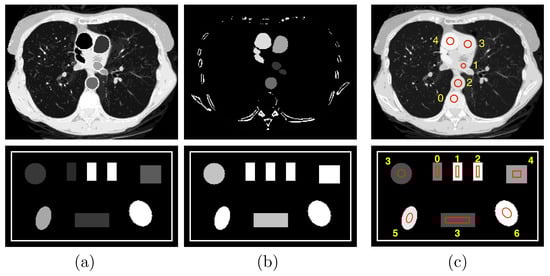

Row 1: (a) water and (b) iodine basis images and (c) VMI at 100 keV of the chest phantom; and row 2: (a) photoelectric effect (PE) and (b) Compton scattering (KN) basis images and (c) VMI at 40 keV of the suitcase phantom. Display windows for the chest phantom are [0, 1.2] for the two basis images and [0, 0.22] cm for the VMI, while those for the suitcase phantom are [0, 0.22] and [0.1, 0.65] cm, respectively.

2.3. Numerical Phantoms Studied

We consider in the work two phantoms, i.e., the chest phantom [] and suitcase phantom [] shown in Figure 2, motivated by their possible implications in medical and security imaging, two distinct DECT imaging applications, and their distinctly different anatomic structures for evaluating algorithm performance. The chest phantom contains four regions of interest (ROIs) 1–4 with iodine-contrast agents at concentrations of 5 mg/mL, 10 mg/mL, 15 mg/mL, and 20 mg/mL, respectively, and other ROIs with mixed materials, such as muscle, lung tissue, and bone; whereas the suitcase phantom includes three ROIs 0–2 of single-element calibration materials, i.e., carbon, aluminum, and calcium, and four more ROIs 3–6 of mixed materials, corresponding to water, ANFO (Ammonium Nitrate and Fuel Oil []), teflon, and PVC, respectively.

In DECT, basis images may be selected according to the task considered. For the chest phantom, to estimate iodine concentrations, we select material-based basis images of water and iodine concentration of 20 mg/mL, with the corresponding ’s obtained from the NIST database []. For the suitcase phantom, in order to estimate effective atomic numbers, we select interaction-based basis images of the photoelectric effect (PE) and Compton scattering (KN) with ’s that are , where E denotes X-ray energy, and obtained with the Klein–Nishina formula [], respectively. The basis images and VMIs of the chest and suitcase phantoms are formed on image arrays of and square pixels of size 0.7 mm, as displayed in rows 1 and 2, respectively, in Figure 2.